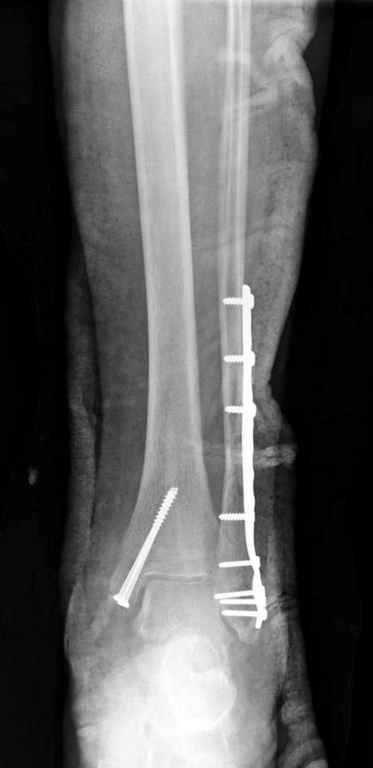

Здесь финальный снимок 73 летней с

сопутствующей шизофренией, латерально бридж

пластину (соединили дистальный конец с диафизом не трогая место перелома) и медиально перкутанно

двумя шурупами. В этам случае без гипса не

обойтись.

Точно, для идеальной репозиции надо открыть передний и задний углы медиальной лодыжки,

сделать ревизию сустава, очистить, убрать интерпозицию, потом только зафиксировать.

Как заметил, по рентгенограмме медиальная лодыжка не очень идеально репонирована. Больная кроме шизофрении страдала другими соматическими заболеваниями, и во время операции от анестезиолога получил рекомендацию поторопиться, поэтому решили закрыто, а так тенденция лечить

открытым методом.